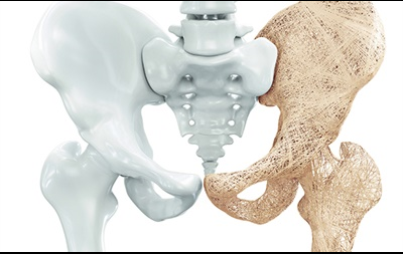

비타민d 부족 증상 1. 뼈 밀도 감소

사람은 나이가 들어감에 따라 뼈의 성장이 점차 느려지고 밀도가 감소 합니다 . 이것은 보통 30 세 전후에 발생 합니다 . 이것이 일어날 때, 환자는 비타민d 의 부족을 경험하고 , 이것은 골 손실을 가속하고 골다공증 관련 합병증을 포함하여 몇몇 증상 을 일으킬 수 있습니다 .